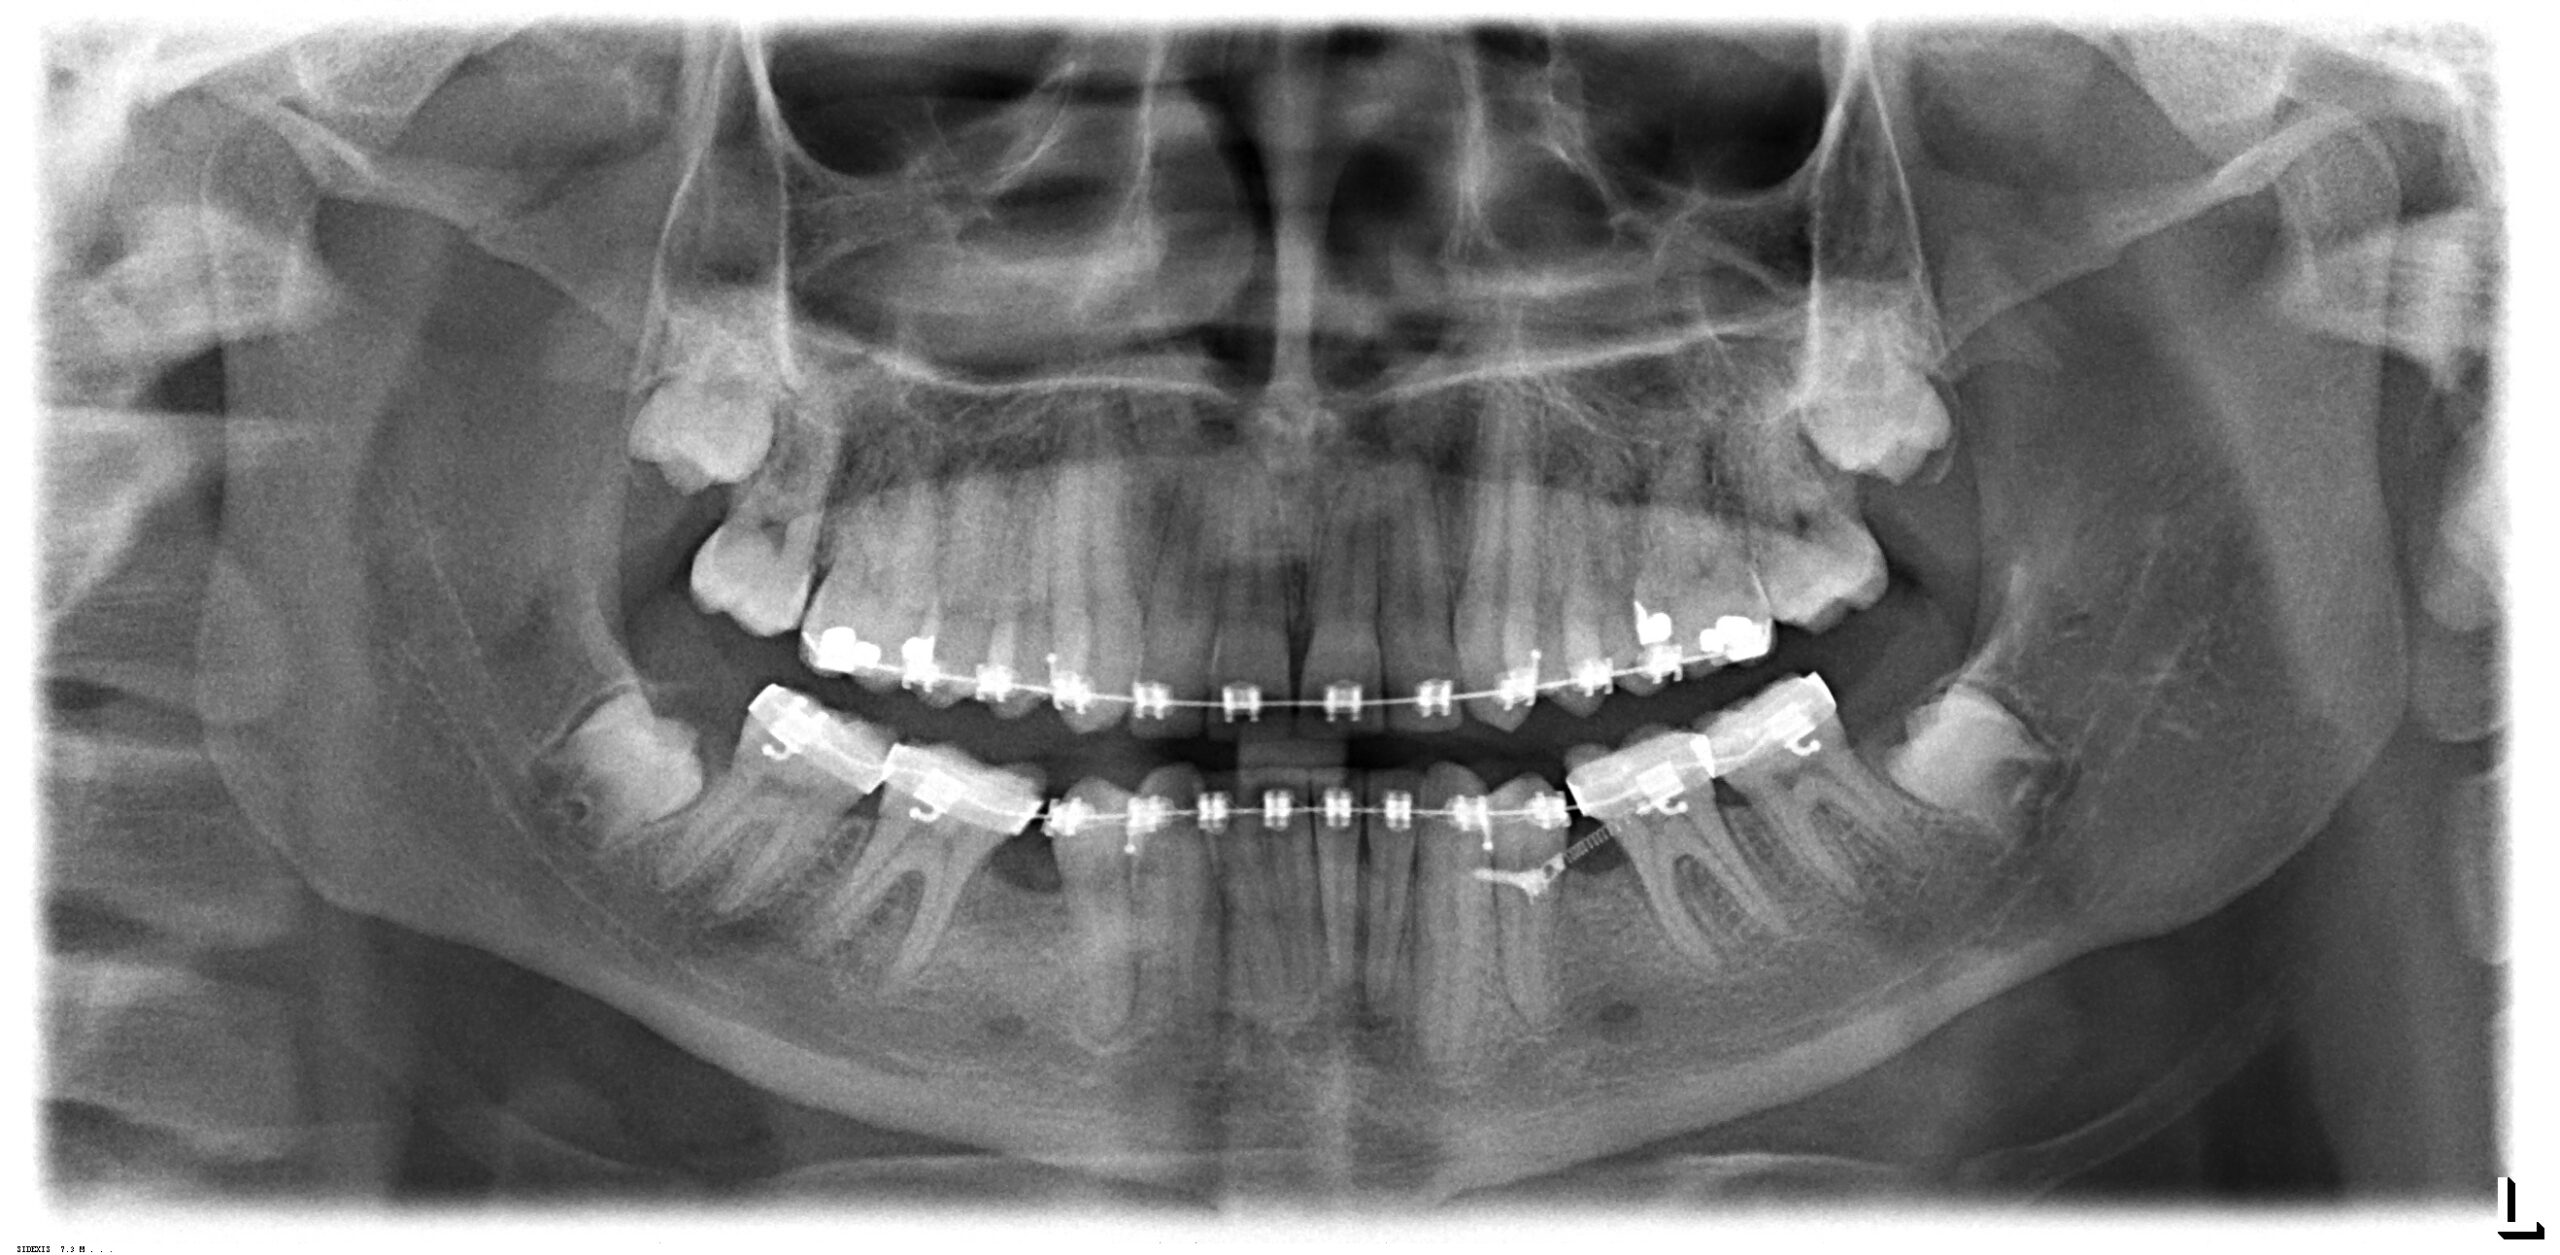

Mikroschrauben

Mikroschrauben stellen eine innovative und bewährte Methode in der Kieferorthopädie zum Erreichen einer maximalen Verankerungssituation bei der Behandlung mit einer festen Spange dar.

Mikroschrauben werden dann angewendet, wenn man bestimmte Bewegungen von Zähnen mit der festen Spange ausführen muss und man einen zusätzlichen Halt benötigt, damit es nicht zu Wechselwirkungen auf die anderen bewegten Zahngruppen kommt. Als Beispiel sei hier ein einseitiger Lückenschluss bei fehlenden oder nicht angelegten Zähnen genannt.